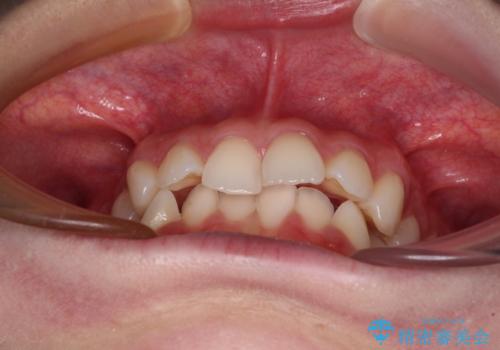

- 前歯のデコボコと下の前歯が隠れてしまう咬み合わせを気にして来院された患者様です。

インビザラインによる上下歯列の拡大と、IPR(歯と歯の間を削る)にるスペースの獲得により、口元のデコボコとディープバイトを改善することとしました。